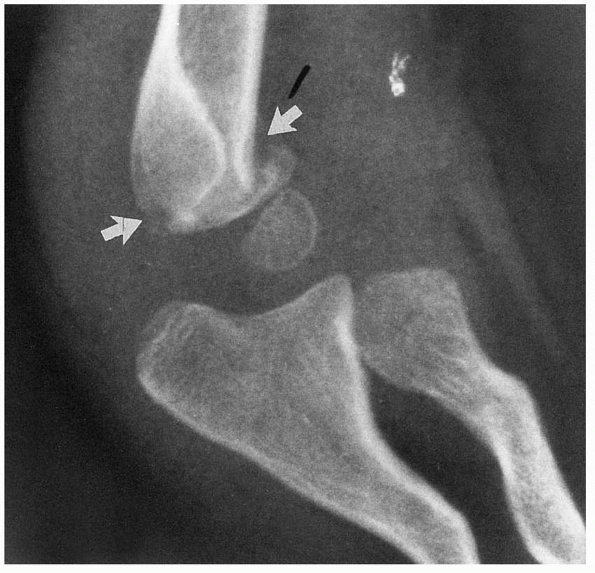

![]() |

FIGURE 14-3

Normal anatomic variant in which there is no bone in the olecranon fossa. Note the minimally displaced radial neck fracture. (Reproduced with permission of Childrens Orthopaedic Center, Los Angeles, CA.) |